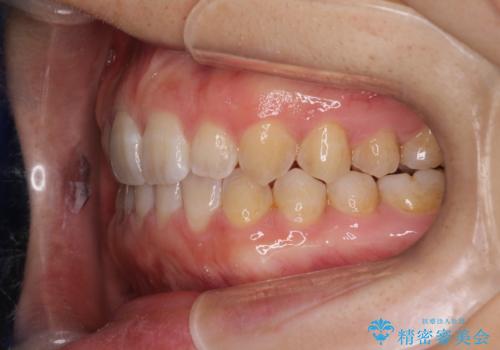

前歯の隙間を閉じたい インビザラインによる矯正

- 上下の前歯に隙間があるとのことで来院されました。

インビザラインにて隙間を閉じる矯正を行いました。

使用時間を守っていただけたので、比較的スムーズに矯正を終了することができました。